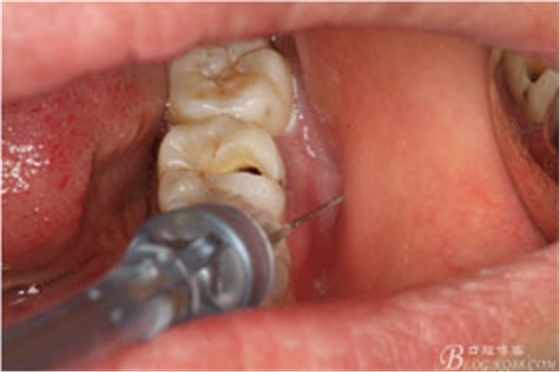

圖4.行下頜無痛阻滯麻醉

圖5.加局部浸潤麻醉